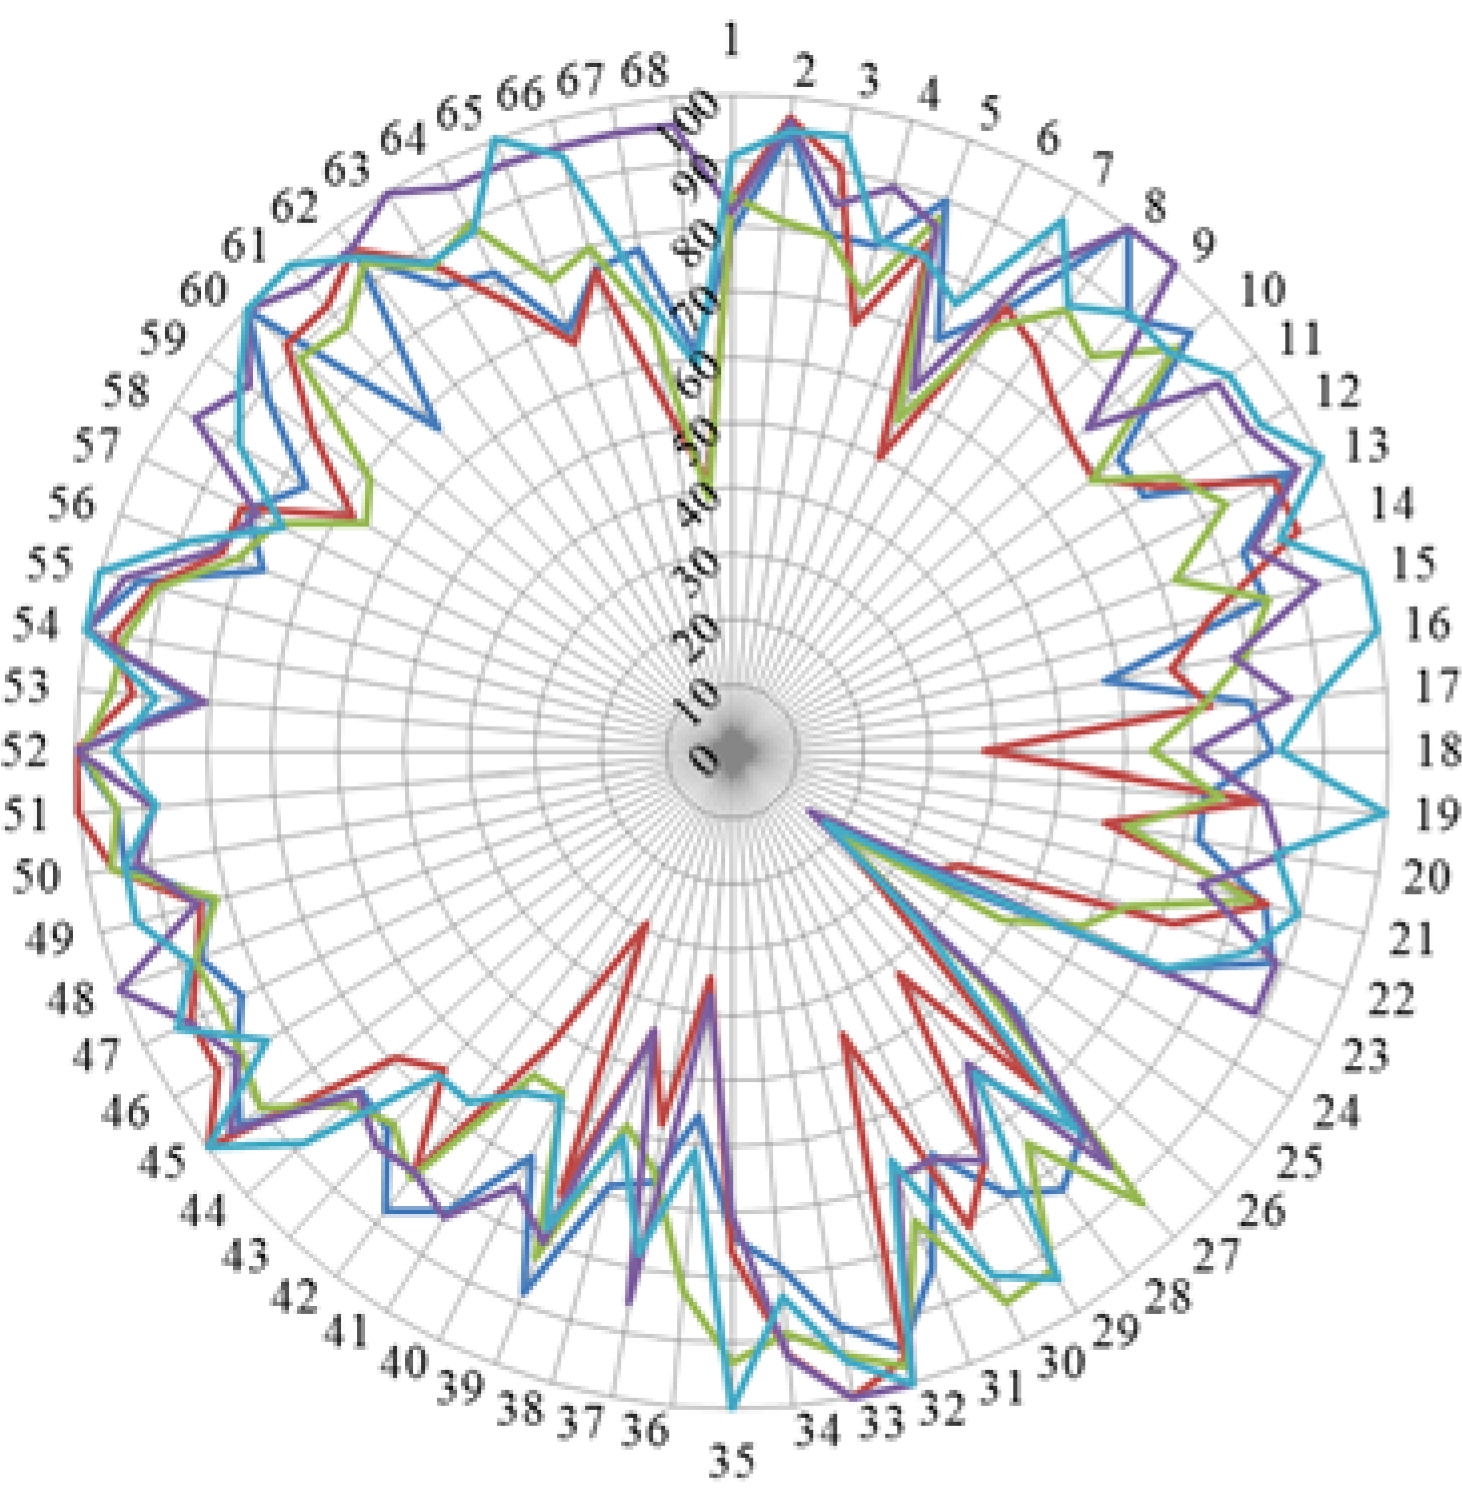

3. Results and Discussion

| N | Competence | Stud. | Acad. | Chi Stud. vs. Acad. | Comm. | Chi Stud. vs. Comm. | |

|---|---|---|---|---|---|---|---|

| Cluster 7. Personal competences: learning and knowledge. | 1 | Ability to identify learning needs and to learn independently (including continuous professional development (CPD)). | 84.5 | 93.7 | 15.7 | 89.8 | 13.1 |

| 2 | Analysis: ability to apply logic to problem solving, evaluating pros and cons and following up on the solution found. | 88.8 | 94.5 | 7.5 | 91.1 | 3.6 | |

| 3 | Synthesis: capacity to gather and critically appraise relevant knowledge and to summarise the key points. | 85.1 | 92.8 | 10.8 | 87.9 | 4.0 | |

| 4 | Capacity to evaluate scientific data in line with current scientific and technological knowledge. | 76.5 | 87.3 | 18.5 | 75.8 | 0.4 | |

| 5 | Ability to interpret preclinical and clinical evidence-based medical science and apply the knowledge to pharmaceutical practice. | 86.0 | 81.2 | 5.2 | 75.9 | 17.3 | |

| 6 | Ability to design and conduct research using appropriate methodology. | 60.6 | 65.4 | 4.9 | 40.2 | 34.3 | |

| 7 | Ability to maintain current knowledge of relevant legislation and codes of pharmacy practice. | 81.7 | 86.3 | 3.3 | 91.7 | 25.7 | |

| Cluster 8. Personal competences: values. | 8 | Demonstrate a professional approach to tasks and human relations. | 86.6 | 91.5 | 7.7 | 94.5 | 23.3 |

| 9 | Demonstrate the ability to maintain confidentiality. | 85.4 | 92.3 | 22.8 | 95.3 | 50.6 | |

| 10 | Take full personal responsibility for patient care and other aspects of one’s practice. | 84.4 | 88.3 | 3.2 | 94.8 | 24.9 | |

| 11 | Inspire the confidence of others in one’s actions and advice. | 77.8 | 83.8 | 8.9 | 88.8 | 13.0 | |

| 12 | Demonstrate high ethical standards. | 85.3 | 95.3 | 43.4 | 95.2 | 24.6 | |

| Cluster 9. Personal competences: communication and organisational skills. | 13 | Effective communication skills (both orally and written). | 91.2 | 93.5 | 3.9 | 94.8 | 4.0 |

| 14 | Effective use of information technology. | 81.1 | 83.8 | 1.4 | 86.1 | 3.8 | |

| 15 | Ability to work effectively as part of a tea. | 86.4 | 83.3 | 6.1 | 89.2 | 1.1 | |

| 16 | Ability to identify and implement legal and professional requirements relating to employment (e.g., for pharmacy technicians) and to safety in the workplace. | 74.8 | 77.9 | 1.9 | 81.0 | 4.5 | |

| 17 | Ability to contribute to the learning and training of staff. | 73.5 | 79.6 | 6.6 | 82.5 | 6.6 | |

| 18 | Ability to design and manage the development processes in the production of medicines. | 61.2 | 60.0 | 0.8 | 43.2 | 38.0 | |

| 19 | Ability to identify and manage risk and quality of service issues. | 77.5 | 76.1 | 4.0 | 79.2 | 2.3 | |

| 20 | Ability to identify the need for new services. | 65.0 | 61.8 | 7.7 | 64.5 | 1.2 | |

| 21 | Ability to communicate in English and/or locally relevant languages. | 84.5 | 79.6 | 2.3 | 74.1 | 16.3 | |

| 22 | Ability to evaluate issues related to quality of service. | 73.0 | 71.0 | 3.5 | 77.9 | 7.4 | |

| 23 | Ability to negotiate, understand a business environment and develop entrepreneurship. | 62.2 | 46.4 | 15.6 | 64.1 | 2.0 | |

| Cluster 10. Personal competences: knowledge of different areas of the science of medicines. | 24 | Plant and animal biology. | 38.8 | 31.1 | 5.1 | 39.3 | 1.0 |

| 25 | Physics. | 20.9 | 25.6 | 2.3 | 21.7 | 0.8 | |

| 26 | General and inorganic chemistry | 53.0 | 45.6 | 3.3 | 43.9 | 5.3 | |

| 27 | Organic and medicinal/pharmaceutical chemistry. | 86.3 | 80.2 | 10.8 | 66.0 | 37.0 | |

| 28 | Analytical chemistry | 65.8 | 60.0 | 3.0 | 41.9 | 46.9 | |

| 29 | General and applied biochemistry (medicinal and clinical). | 85.4 | 74.2 | 10.8 | 68.8 | 22.6 | |

| 30 | Anatomy and physiology; medical terminology. | 85.2 | 75.8 | 11.2 | 88.7 | 3.3 | |

| 31 | Microbiology. | 72.2 | 67.0 | 3.3 | 72.2 | 1.5 | |

| 32 | Pharmacology including pharmacokinetics. | 97.5 | 95.6 | 3.7 | 94.7 | 3.0 | |

| 33 | Pharmacotherapy and pharmaco-epidemiology. | 95.3 | 92.5 | 3.1 | 94.3 | 2.2 | |

| 34 | Pharmaceutical technology including analyses of medicinal products. | 86.9 | 89.0 | 1.4 | 62.0 | 50.8 | |

| 35 | Toxicology. | 85.0 | 84.4 | 17.3 | 74.0 | 27.7 | |

| 36 | Pharmacognosy. | 65.9 | 52.9 | 11.3 | 66.5 | 2.1 | |

| 37 | Legislation and professional ethics. | 71.7 | 88.8 | 26.8 | 89.5 | 44.2 | |

| Cluster 11. Personal competences: understanding of industrial pharmacy. | 38 | Current knowledge of design, synthesis, isolation, characterisation and biological evaluation of active substances. | 59.9 | 57.5 | 1.9 | 41.7 | 34.2 |

| 39 | Current knowledge of good manufacturing practice (GMP) and of good laboratory practice (GLP). | 79.2 | 75.4 | 1.6 | 59.4 | 29.8 | |

| 40 | Current knowledge of European directives on qualified persons (QPs). | 55.3 | 59.2 | 1.8 | 43.7 | 39.9 | |

| 41 | Current knowledge of drug registration, licensing and marketing. | 65.7 | 72.1 | 4.6 | 55.7 | 11.9 | |

| 42 | Current knowledge of good clinical practice (GCP). | 78.1 | 68.2 | 9.1 | 64.5 | 23.8 | |

| Cluster 12. Patient care competences: patient consultation and assessment. | 43 | Ability to perform and interpret medical laboratory tests. | 72.0 | 65.3 | 5.9 | 65.5 | 6.0 |

| 44 | Ability to perform appropriate diagnostic or physiological tests to inform clinical decision making e.g., measurement of blood pressure. | 76.1 | 64.5 | 17.3 | 73.6 | 7.8 | |

| 45 | Ability to recognise when referral to another member of the healthcare team is needed because a potential clinical problem is identified (pharmaceutical, medical, psychological or social). | 91.7 | 89.1 | 2.2 | 91.7 | 9.5 | |

| Cluster 13. Patient care competences: need for drug treatment. | 46 | Retrieval and interpretation of relevant information on the patient’s clinical background. | 85.6 | 79.3 | 8.4 | 84.0 | 0.7 |

| 47 | Retrieval and interpretation of an accurate and comprehensive drug history if and when required. | 87.6 | 89.4 | 5.1 | 91.5 | 2.3 | |

| 48 | Identification of non-adherence and implementation of appropriate patient intervention. | 87.1 | 85.8 | 6.1 | 86.8 | 24.5 | |

| 49 | Ability to advise to physicians and—in some cases—prescribe medication. | 81.9 | 80.7 | 2.5 | 87.6 | 5.3 | |

| Cluster 14. Patient care competences: drug interactions. | 50 | Identification, understanding and prioritisation of drug-drug interactions at a molecular level (e.g., use of codeine with paracetamol). | 91.4 | 91.8 | 1.1 | 91.6 | 0.6 |

| 51 | Identification, understanding, and prioritisation of drug-patient interactions, including those that preclude or require the use of a specific drug (e.g., trastuzumab for treatment of breast cancer in women with HER2 overexpression). | 91.4 | 87.7 | 4.4 | 89.7 | 5.0 | |

| 52 | Identification, understanding, and prioritisation of drug-disease interactions (e.g., NSAIDs in heart failure). | 97.0 | 94.5 | 8.9 | 96.6 | 2.7 | |

| Cluster 15. Patient care competences: provision of drug product. | 53 | Familiarity with the bio-pharmaceutical, pharmacodynamic and pharmacokinetic activity of a substance in the body. | 89.3 | 90.8 | 3.5 | 81.2 | 11.6 |

| 54 | Supply of appropriate medicines taking into account dose, correct formulation, concentration, administration route and timing. | 94.3 | 96.3 | 16.3 | 94.9 | 18.0 | |

| 55 | Critical evaluation of the prescription to ensure that it is clinically appropriate and legal. | 93.9 | 94.1 | 6.6 | 94.0 | 11.1 | |

| 56 | Familiarity with the supply chain of medicines and the ability to ensure timely flow of drug products to the patient. | 81.6 | 78.6 | 4.5 | 84.6 | 11.3 | |

| 57 | Ability to manufacture medicinal products that are not commercially available. | 74.1 | 69.0 | 1.5 | 60.5 | 21.2 | |

| Cluster 16. Patient care competences: patient education. | 58 | Promotion of public health in collaboration with other actors in the healthcare system. | 75.8 | 75.1 | 1.1 | 82.6 | 5.9 |

| 59 | Provision of appropriate lifestyle advice on smoking, obesity, etc. | 76.9 | 71.0 | 3.8 | 80.9 | 4.7 | |

| 60 | Provision of appropriate advice on resistance to antibiotics and similar public health issues. | 90.3 | 89.4 | 5.2 | 93.1 | 3.6 | |

| Cluster 17. Patient care competences: provision of information and service. | 61 | Ability to use effective consultations to identify the patient’s need for information. | 85.6 | 81.1 | 3.1 | 90.9 | 11.1 |

| 62 | Provision of accurate and appropriate information on prescription medicines. | 92.7 | 89.3 | 8.0 | 94.4 | 11.0 | |

| 63 | Provision of informed support for patients in selection and use of non-prescription medicines for minor ailments (e.g., cough remedies). | 85.7 | 89.4 | 1.7 | 94.0 | 14.4 | |

| Cluster 18. Patient care competences: monitoring of drug therapy. | 64 | Identification and prioritisation of problems in the management of medicines in a timely manner and with sufficient efficacy to ensure patient safety. | 88.5 | 87.9 | 8.2 | 93.0 | 8.7 |

| 65 | Ability to monitor and report to all concerned in a timely manner, and in accordance with current regulatory guidelines on Good Pharmacovigilance Practices (GVPs), Adverse Drug Events and Reactions (ADEs and ADRs). | 79.8 | 80.9 | 5.0 | 83.4 | 3.3 | |

| 66 | Undertaking of a critical evaluation of prescribed medicines to confirm that current clinical guidelines are appropriately applied. | 80.7 | 81.6 | 0.3 | 80.6 | 4.5 | |

| Cluster 19. Patient care competences: evaluation of outcomes. | 67 | Assessment of outcomes on the monitoring of patient care and follow-up interventions. | 73.3 | 73.7 | 0.5 | 79.0 | 4.4 |

| 68 | Evaluation of cost effectiveness of treatment. | 53.3 | 57.7 | 2.1 | 61.2 | 4.8 |